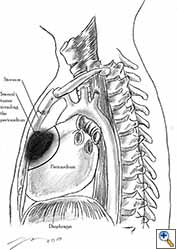

Pericardial reconstruction is indicated after extrapleural pneumonectomy for diffuse malignant pleural mesothelioma. Right-sided pericardioplasty is performed to prevent cardiac dislocation as discussed above. Left sided pericardial defects that result after extrapleural pneumonectomies are large and there is no risk of cardiac strangulation, but reconstruction is recommended in order to prevent constrictive epicarditis (Figure 3) [4].

Video 1 depicts a pericardial reconstruction with Marlex after a right completion pneumonectomy with pericardiectomy for lung adenocarcinoma (see also Figure 1). The technique of pericardial reconstruction after the resection of invasive mediastinal tumours is illustrated in Figures 8a-c). Video 2 depicts a pericardial reconstruction with Mersilene mesh after the resection of a malignant thymoma invading the anterior pericardium (see also Figure 4b). The technique of right pericardial reconstruction after extrapleural pneumonectomy is illustrated in Figures 9a and 9b). Video 3 depicts a pericardial reconstruction using Gore-Tex Dual Mesh after a left extrapleural pneumonectomy (see also Figure 3). Care must be taken to prevent constriction (Figure 10).